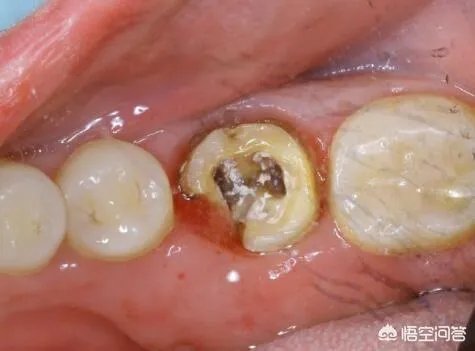

虫牙就是龋齿是致龋性食物糖贴附于牙面,足够的时间在菌斑深层,侵袭牙齿破坏有机质,产生龋洞。看您现在牙齿的情况呢。如果目前只剩下残根(牙冠消失只剩下牙根)、残冠(牙冠是个空壳)需要拔掉,因为他们已经不能用力咬合了。治疗方法就是镶牙或者种植,一般建议种植,种植能恢复本来咀嚼功能的90%,在口内没有异物感,使用时间长。如果是龋齿没有伤到神经,直接去腐充填就可以啦。如果龋坏牙冷热敏感伤到牙神经了就需要根管治疗,也就是俗称杀神经了,牙齿没有了神经就会脆弱,就像大叔没有根部一样,所以特别是槽牙,一旦杀神经的牙齿可以做牙冠保护,会把牙齿磨小一些,套上牙冠,就像牙齿披了铠甲一样就会耐用很多。不然牙齿最后劈裂还是需要拔掉,种植或镶牙。

浅龋和中龋我们一般只需要去掉腐坏的物质,进行补牙就好,而对于深龋,则需要进行根管治疗后,然后填充即可,但一般医生都会建议做个牙冠,因为根管治疗后牙齿没有了牙髓根管里血管的血液供给,变得比较脆,咬硬东西容易崩裂,如果崩裂了,只能到拔牙的地步了。

如果是轻度缺损的蛀牙,可以清除腐败物质后进行补牙。若是缺损程度已经危及牙髓,或导致牙髓已受细菌感染,则需要进行根管治疗。

根管治疗也就是平常所说的“抽神经”,先将牙髓腔中的牙神经用药物杀死,再利用专门的医疗器械将神经、细菌、其他腐败物质等清除出牙体,最后进行充填。有的牙冠缺损过多的,则需要做牙冠保护。